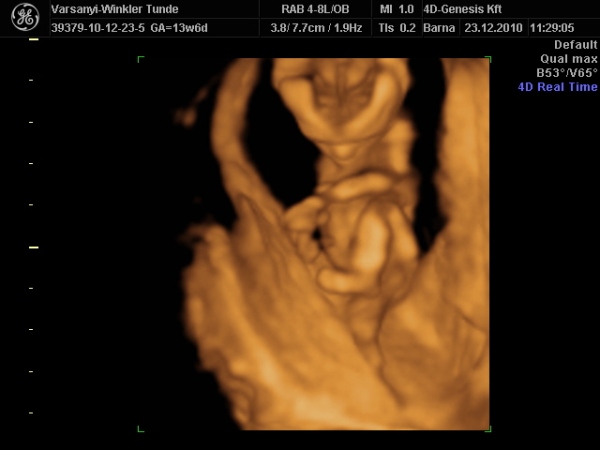

)2010.12.23 11:37